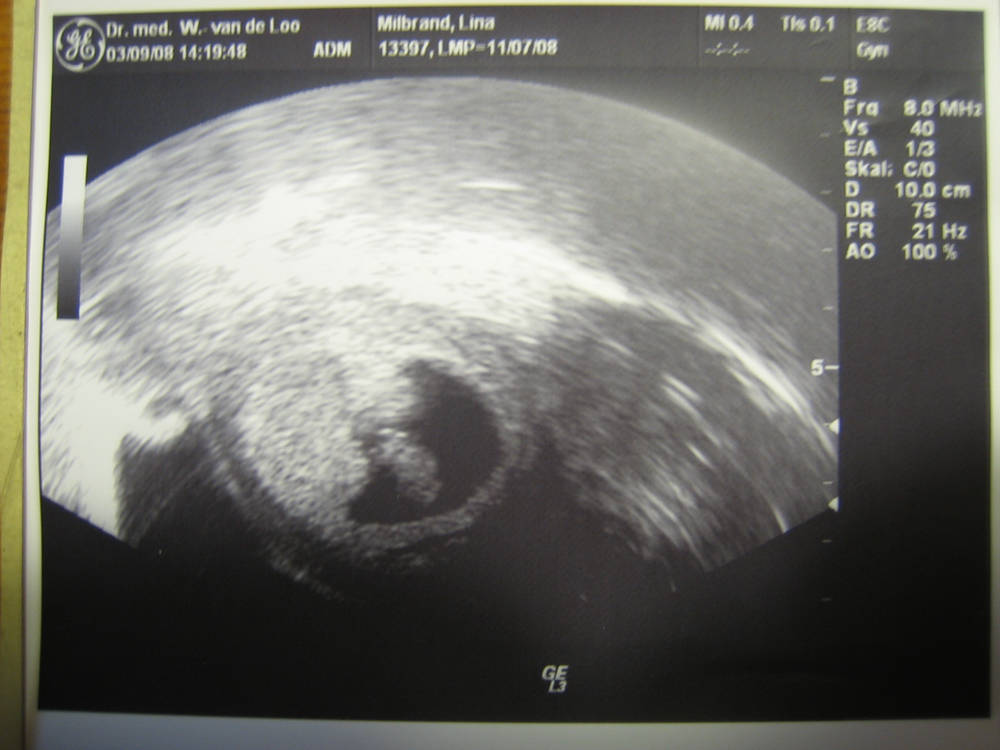

Lotte Hedwig Hoppe (* 11.04.2009) zu Frida